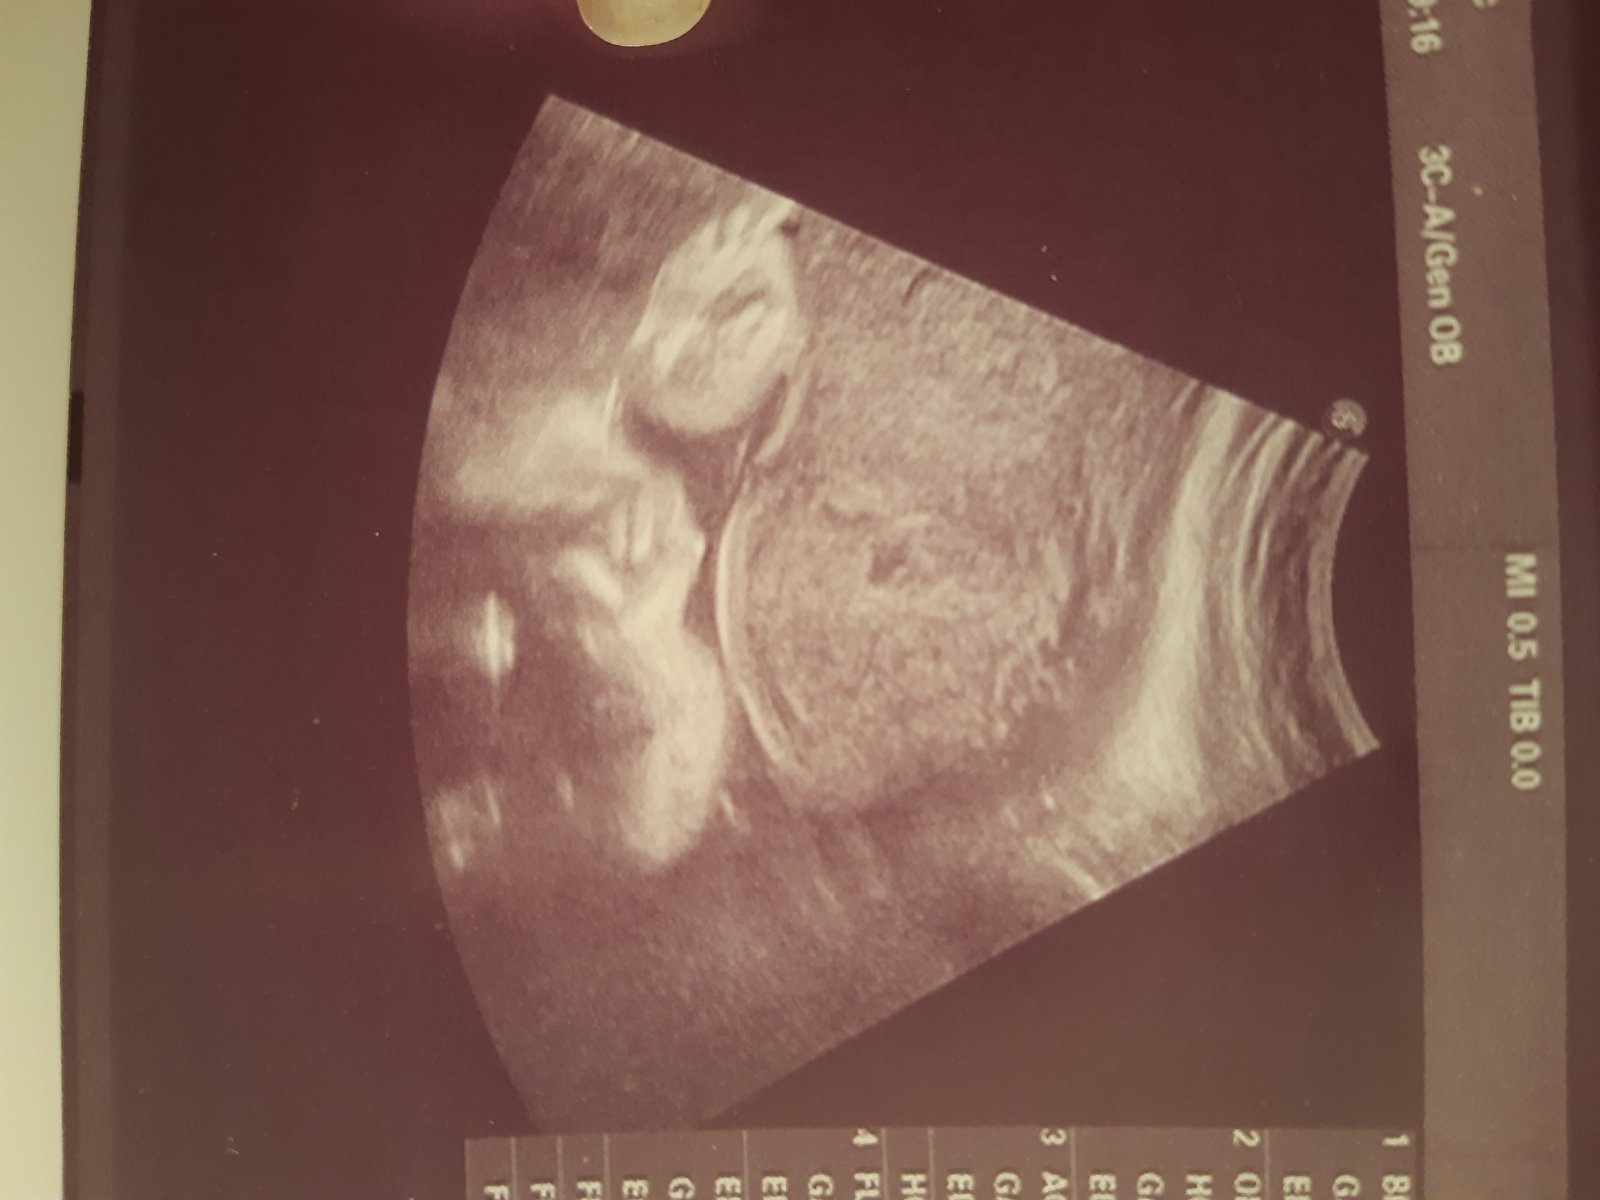

Ta na obrázku je zachycena podle mě ruka ✋ 😉 Ale těžko hodnotit, když člověk nevidí další souvislosti. UZ obraz je 2D obraz v čase, takže se z jedno obrázku nedá absolutně soudit. Jinak důvěru v doktora ztrácet nemusíš. Prostě na UZ nejsou některé věci jiste. Vim to z praxe, UZ mě živí 😉

Jsem jenom laik, ale jestli má být na fotce pohlaví, tak uprostřed jde krásně vidět kávové zrnko = holka.

Doufám, že nebudím plané naděje, ale jestli to má být foto pohlaví, tak za mě holka.

@lenapol me tonprijde jako dost nešikovně fotka na pohlaví ale vidím.spis zrno. Ale takhle ke koncin jsou ty ultrazvuku těžký jak tam ma mimco čím dál min místa. Ja mam doma syna, který se ne a ne ukázat az někdy ve 28tt najednou na nas vykoukl pinda pres celou obrazovku a to bylo z boku pak zajel mezi nožky a potvrdil to. Ted cekam holcicku ( mimochodem na kazde kontrole se ptám zda to je stále holka mam sice neutrální obleceni po synovi ale taky uz mam mraky ciste holciciho a co hlavne dětský pokoj zařízený s holcicima doplnkama 🤣) ale proste furt 100% je az porod ultrazvuk je stále. Ale teda po přečtení zkusenosti mam uplne hrůzu co ze me do toho měsíce vyleze 🤣🤣🤣🤣